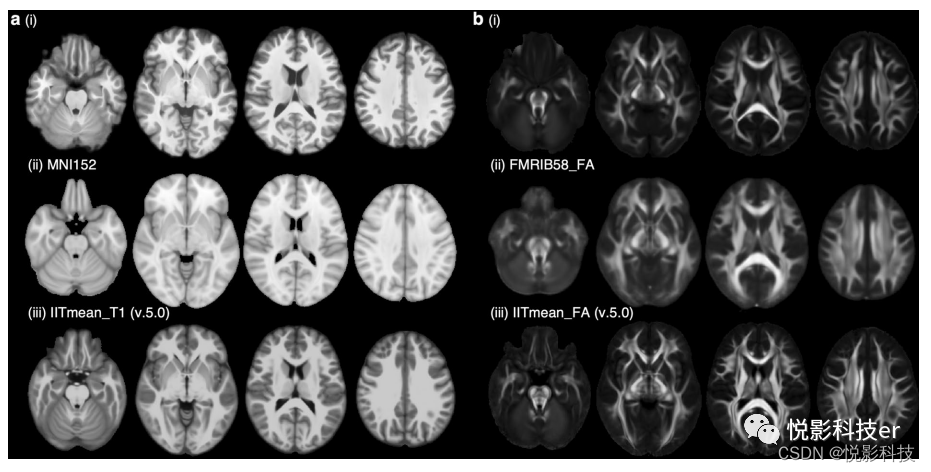

4.技术验证

图8展示了我们的结构地图集,包括t1加权地图集(图a)和HARDI GFA地图集(图b),并与基于不同种族受试者创建的成熟成人地图集进行了比较。在视觉上,我们的t1加权图谱(面板a, (i))比MNI152图谱(面板a, (ii))具有更好的对比度。我们T1加权图谱中脑沟和脑回的模式与MNI152图谱(图a, (ii))和IIT T1图谱47(图a, (iii))中的模式基本一致。另一方面,我们的HARDI GFA图谱(图b, (i))的白质解剖细节比FMRIB58 FA图谱(FMRIB,牛津,英国)更清晰(图b, (ii))。主要的白质束,包括胼胝体、放射状冠、内囊、外囊、上、下纵束,以及小的特征,包括前连合和浅表白质,在我们的HARDI GFA图谱中也观察到了(图b, (iii))。

图8 结构图集的比较